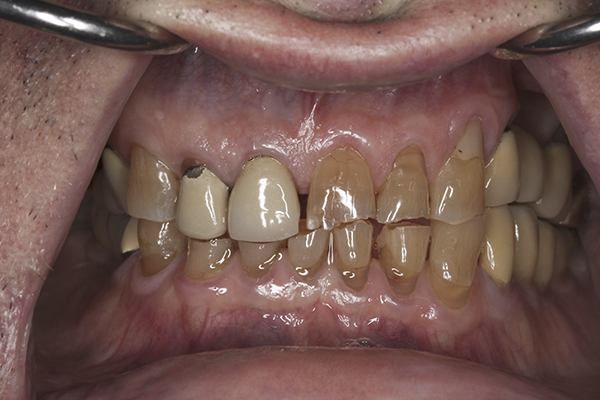

(6.) Preoperative right lateral, open view.

Figure 6

(9.) Preoperative right lateral, closed view.

Figure 9